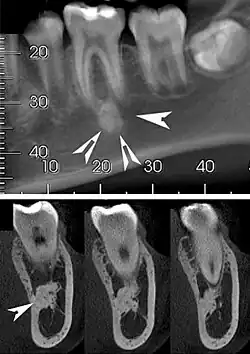

Top: A hyperdense round lesion located under the apex of a non-infected tooth. Bottom: The lesion is separated from the root of the adjacent tooth by a visible periodontal membrane.[1]

Idiopathic osteosclerosis, also known as enostosis or dense bone island, is a condition which may be found around the roots of a tooth, usually a premolar or molar.[2] It is usually painless and found during routine radiographs as an amorphous radiopaque (light) area around a tooth. There is no sign of inflammation of the tooth, and if the island is associated with the root the periodontal ligament space is preserved.[2]

Well defined, rounded or triangular radiodensity, that is uniformly opaque. There is no lucent component. Found near the root apex or in the inter-radicular area. Root resorption and tooth movement are rare. If it blends into bone cortices, it does so with no expansion or thinning.[2]